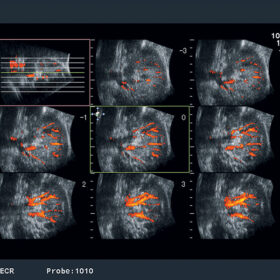

Women’s Healthcare

- Spatio-temporal Image Correlation (STIC)

- Dynamic Slow-motion Display (DSD)

- Volume Slice Imaging (VSI)

- Automated Nuchal Translucency (NT) Measurement

- Real-time Tissue Elastography

- Small part 3D Imaging

- Multi-follicle Volume (MFV)

- eFLOW

RT-3D (4D)

Aloka ASU-1010 3D/4D Convex

Aloka ASU-1012 3D/4D Vaginal